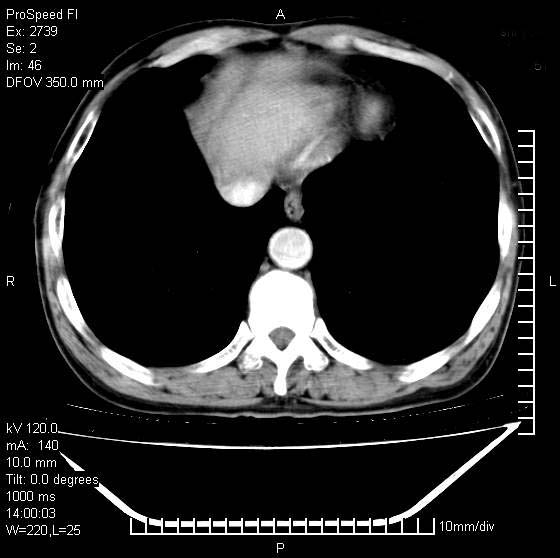

以下是引用andymaomao在2007-12-7 15:54:00的发言:[br]1.双上肺陈旧肺tb灶;[br]2.双中上肺矽肺;[br]3.双肺气肿;[br]4.图中箭头所指乃下腔静脉。

以下是引用山之魂海之韵在2007-12-7 18:59:00的发言:[br]支持矽肺,左肺上叶陈旧性结核,肺气肿。箭头所指乃下腔静脉。下腔静脉显影比主动脉显影迟,增强动脉后迟可以是不均匀的。

以下是引用chengjiaqiu1在2007-12-7 17:49:00的发言:[br]矽肺,左肺上叶陈旧性结核,肺气肿。中箭头所指乃下腔静脉。